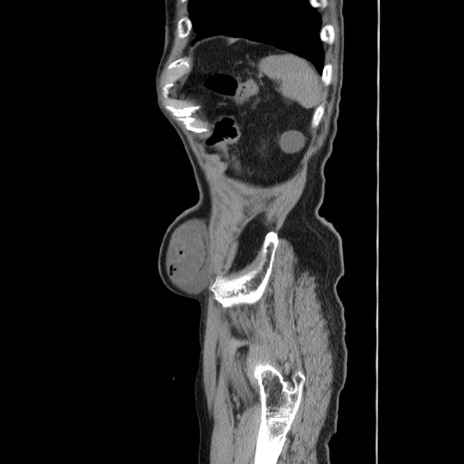

症例24(矢状断像)

【症例】80歳代男性

【主訴】左側腹部痛、嘔吐

【現病歴】本日早朝より左腹部に痛みあり。昼頃嘔吐認めたため、救急要請。

【既往歴】直腸癌(Mile手術)、胆摘

【身体所見】意識清明、BT 35.9℃、BP 221/93mmHg、SpO2 97%(RA) 、腹部:左ストーマ周囲に限局性の腹部膨隆あり。 膨隆部自発痛・圧痛あり・軟。

【データ】WBC 7700、CRP 0.09